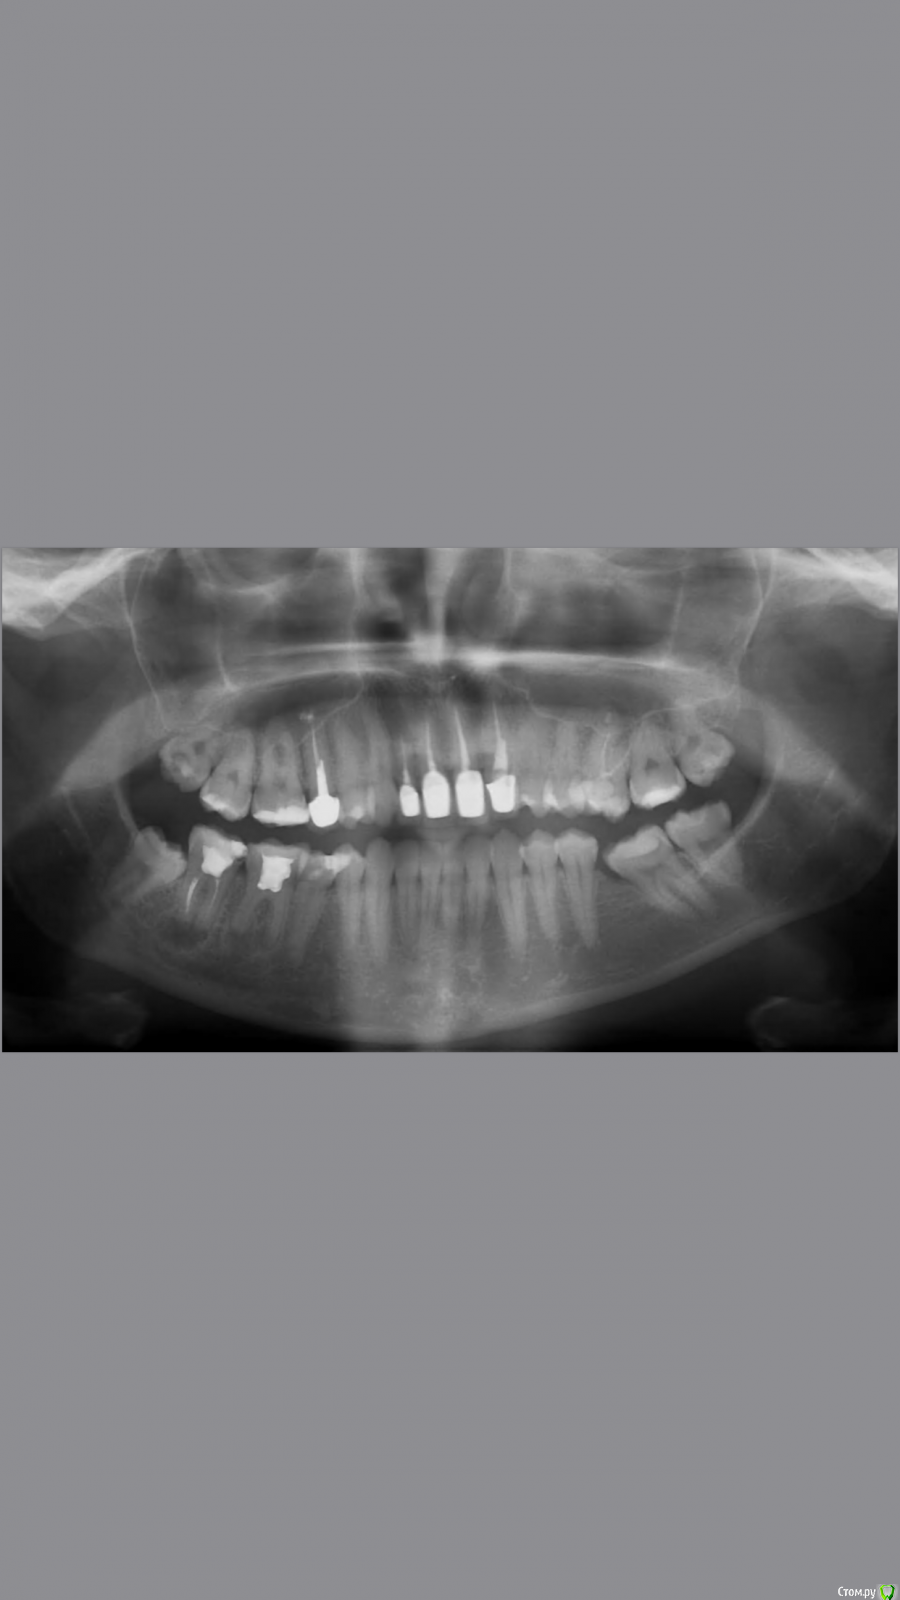

johniola Опубликовано 8 июня, 2019 Поделиться Опубликовано 8 июня, 2019 Реэндо+орто+протезирование 1 Ссылка на комментарий

Monkey Опубликовано 19 июня, 2019 Поделиться Опубликовано 19 июня, 2019 Добрый вечер.Коллеги помогите грамотно скласть план лечения?С чего начинать ,терапия,ортодонтия ортопедияСанация, удаление 8-х, ортодонтическое лечение с раскрытием места 36,23 (заодно и среднюю линию откорректируете), протезирование Ссылка на комментарий